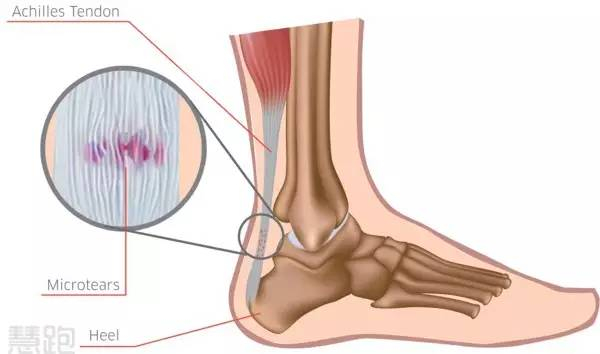

跟腱疼痛属于非常典型的过度使用损伤。在跑步过程中,跟腱要承受高达8-12倍的体重作用,也就是说跟腱受到了巨大力量的反复牵扯,导致轻微创伤反复发生,引发了跟腱力学衰竭,并随之发生结构改变,疼痛自然难以避免。

跟腱病频繁发生在两个位置:(1)跟腱腱体上疼痛(距离跟腱止点近端2-6cm);(2)跟腱止点处疼痛。其中,跟腱腱体的疼痛比较常见。我们今天要讨论的主要是腱体疼痛,止点疼痛更为复杂。